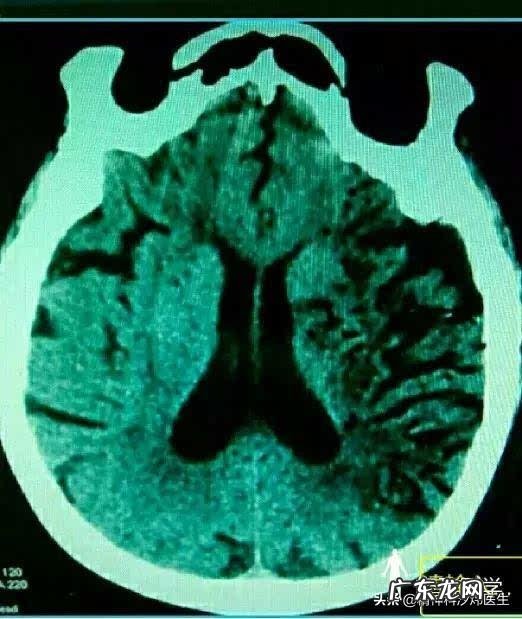

得了精神分裂,会不会导致小脑萎缩?你好,精神分裂症会不会导致小脑萎缩,答案是,很可能,我们可以用数据说话 。

有学者对52例精神分裂症患者进行头颅核磁检查,经研究发现:有34例出现脑萎缩。这其中, 脑室扩大13例, 脑室、脑池和脑沟扩大10例, 脑沟增宽、脑回缩小者7例, 小脑萎缩4例, 大脑皮质和小脑均有萎缩者11例 。